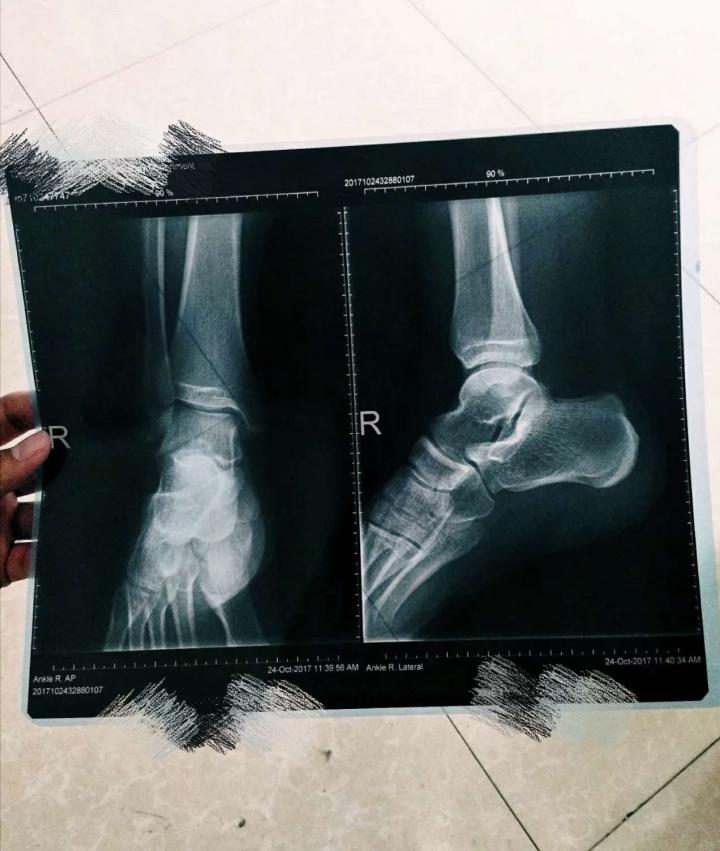

脚踝[伤心]